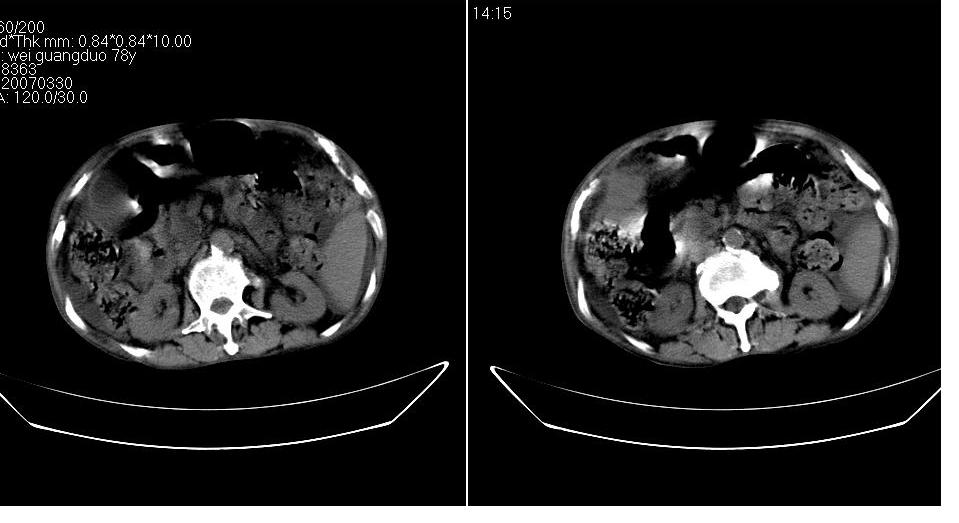

男 78岁,全身黄染,病人家属拒绝增强。

胆总管下端梗阻(原因待查)伴肝内外胆管扩张、胆囊积水。

肝周 脾周 胆囊窝内明显积液,胆囊扩大,胆囊壁模糊,肝内胆管扩张。考虑;胆囊癌周边侵润伴腹水。

1、梗阻性黄疸(胆总管下段病变或十二指肠病变)。

2、胆囊炎,腹水。

3、肝内钙化灶(寄生虫?)。